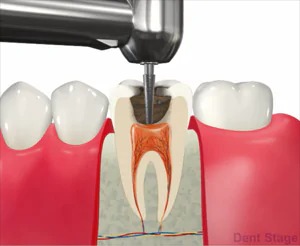

むし歯が深くまで進んで神経にまで達してしまった場合に行う治療で、歯の根の中をきれいに掃除して、ばい菌が入らないように薬を詰めて密閉します。歯の根っこの内部には、神経や血管が入っています。ここを根管と言います。

むし歯が進行して、根の中に菌が入ると汚れがたまります。汚れている根管を綺麗にするために、ファイルという器具で掃除し、消毒薬を使って汚れを洗い流し、治療と治療の間で菌を増やさない様に薬を詰めます。最終的に根管が綺麗になったら、細菌が繁殖しない様にお薬を詰めて終わりになります。この治療をしっかり行う事により、患者様の歯を更に長生きさせることができます。

3抜髄

炎症を起こしてしまった神経を抜いていきます。この時使用するのはファイルというヤスリのようなものを使用します。